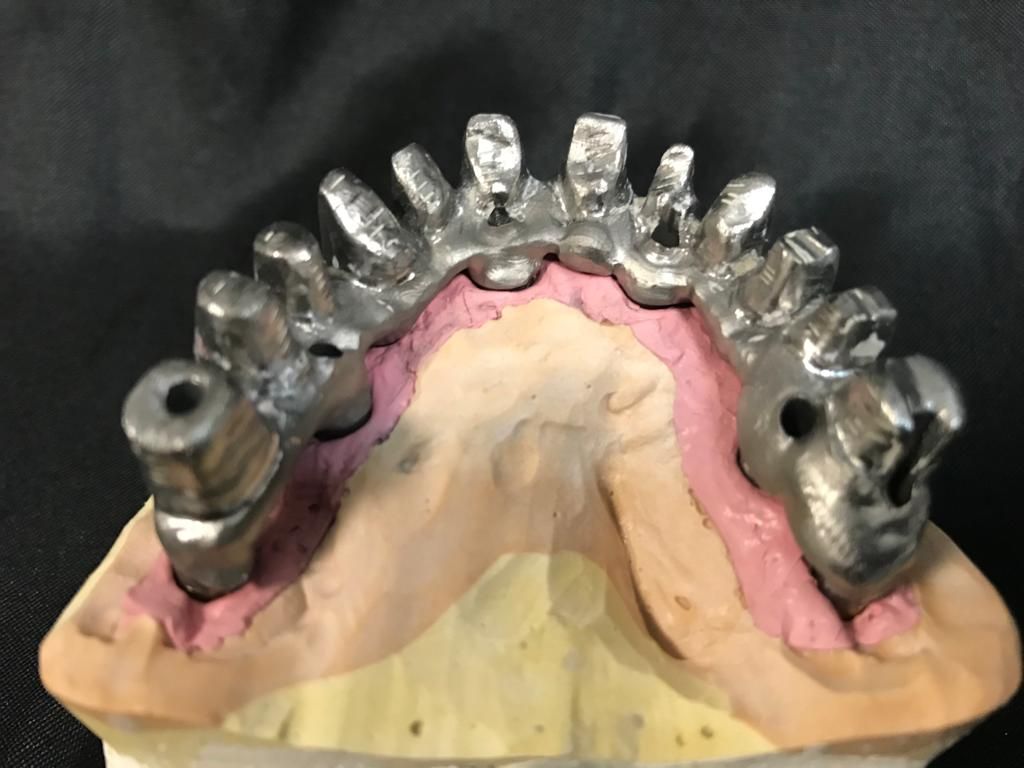

Avvalendoci di validi collaboratori e strumenti all'avanguardia, da Studio Dentistico Amerio ad Ala forniamo servizi specialistici di odontoiatria infantile, chirurgia parodontale, implantologia osteointegrata ed estetica dentale.

Inoltre consigliamo controlli frequenti e periodici associati a detartrasi annuale e, quando necessario, trattamenti dentistici su misura, come lo sbiancamento con laser odontoiatrico, la cura delle malattie gengivali, l'applicazione di faccette in ceramica e le terapie di ortodonzia con apparecchio dentale.